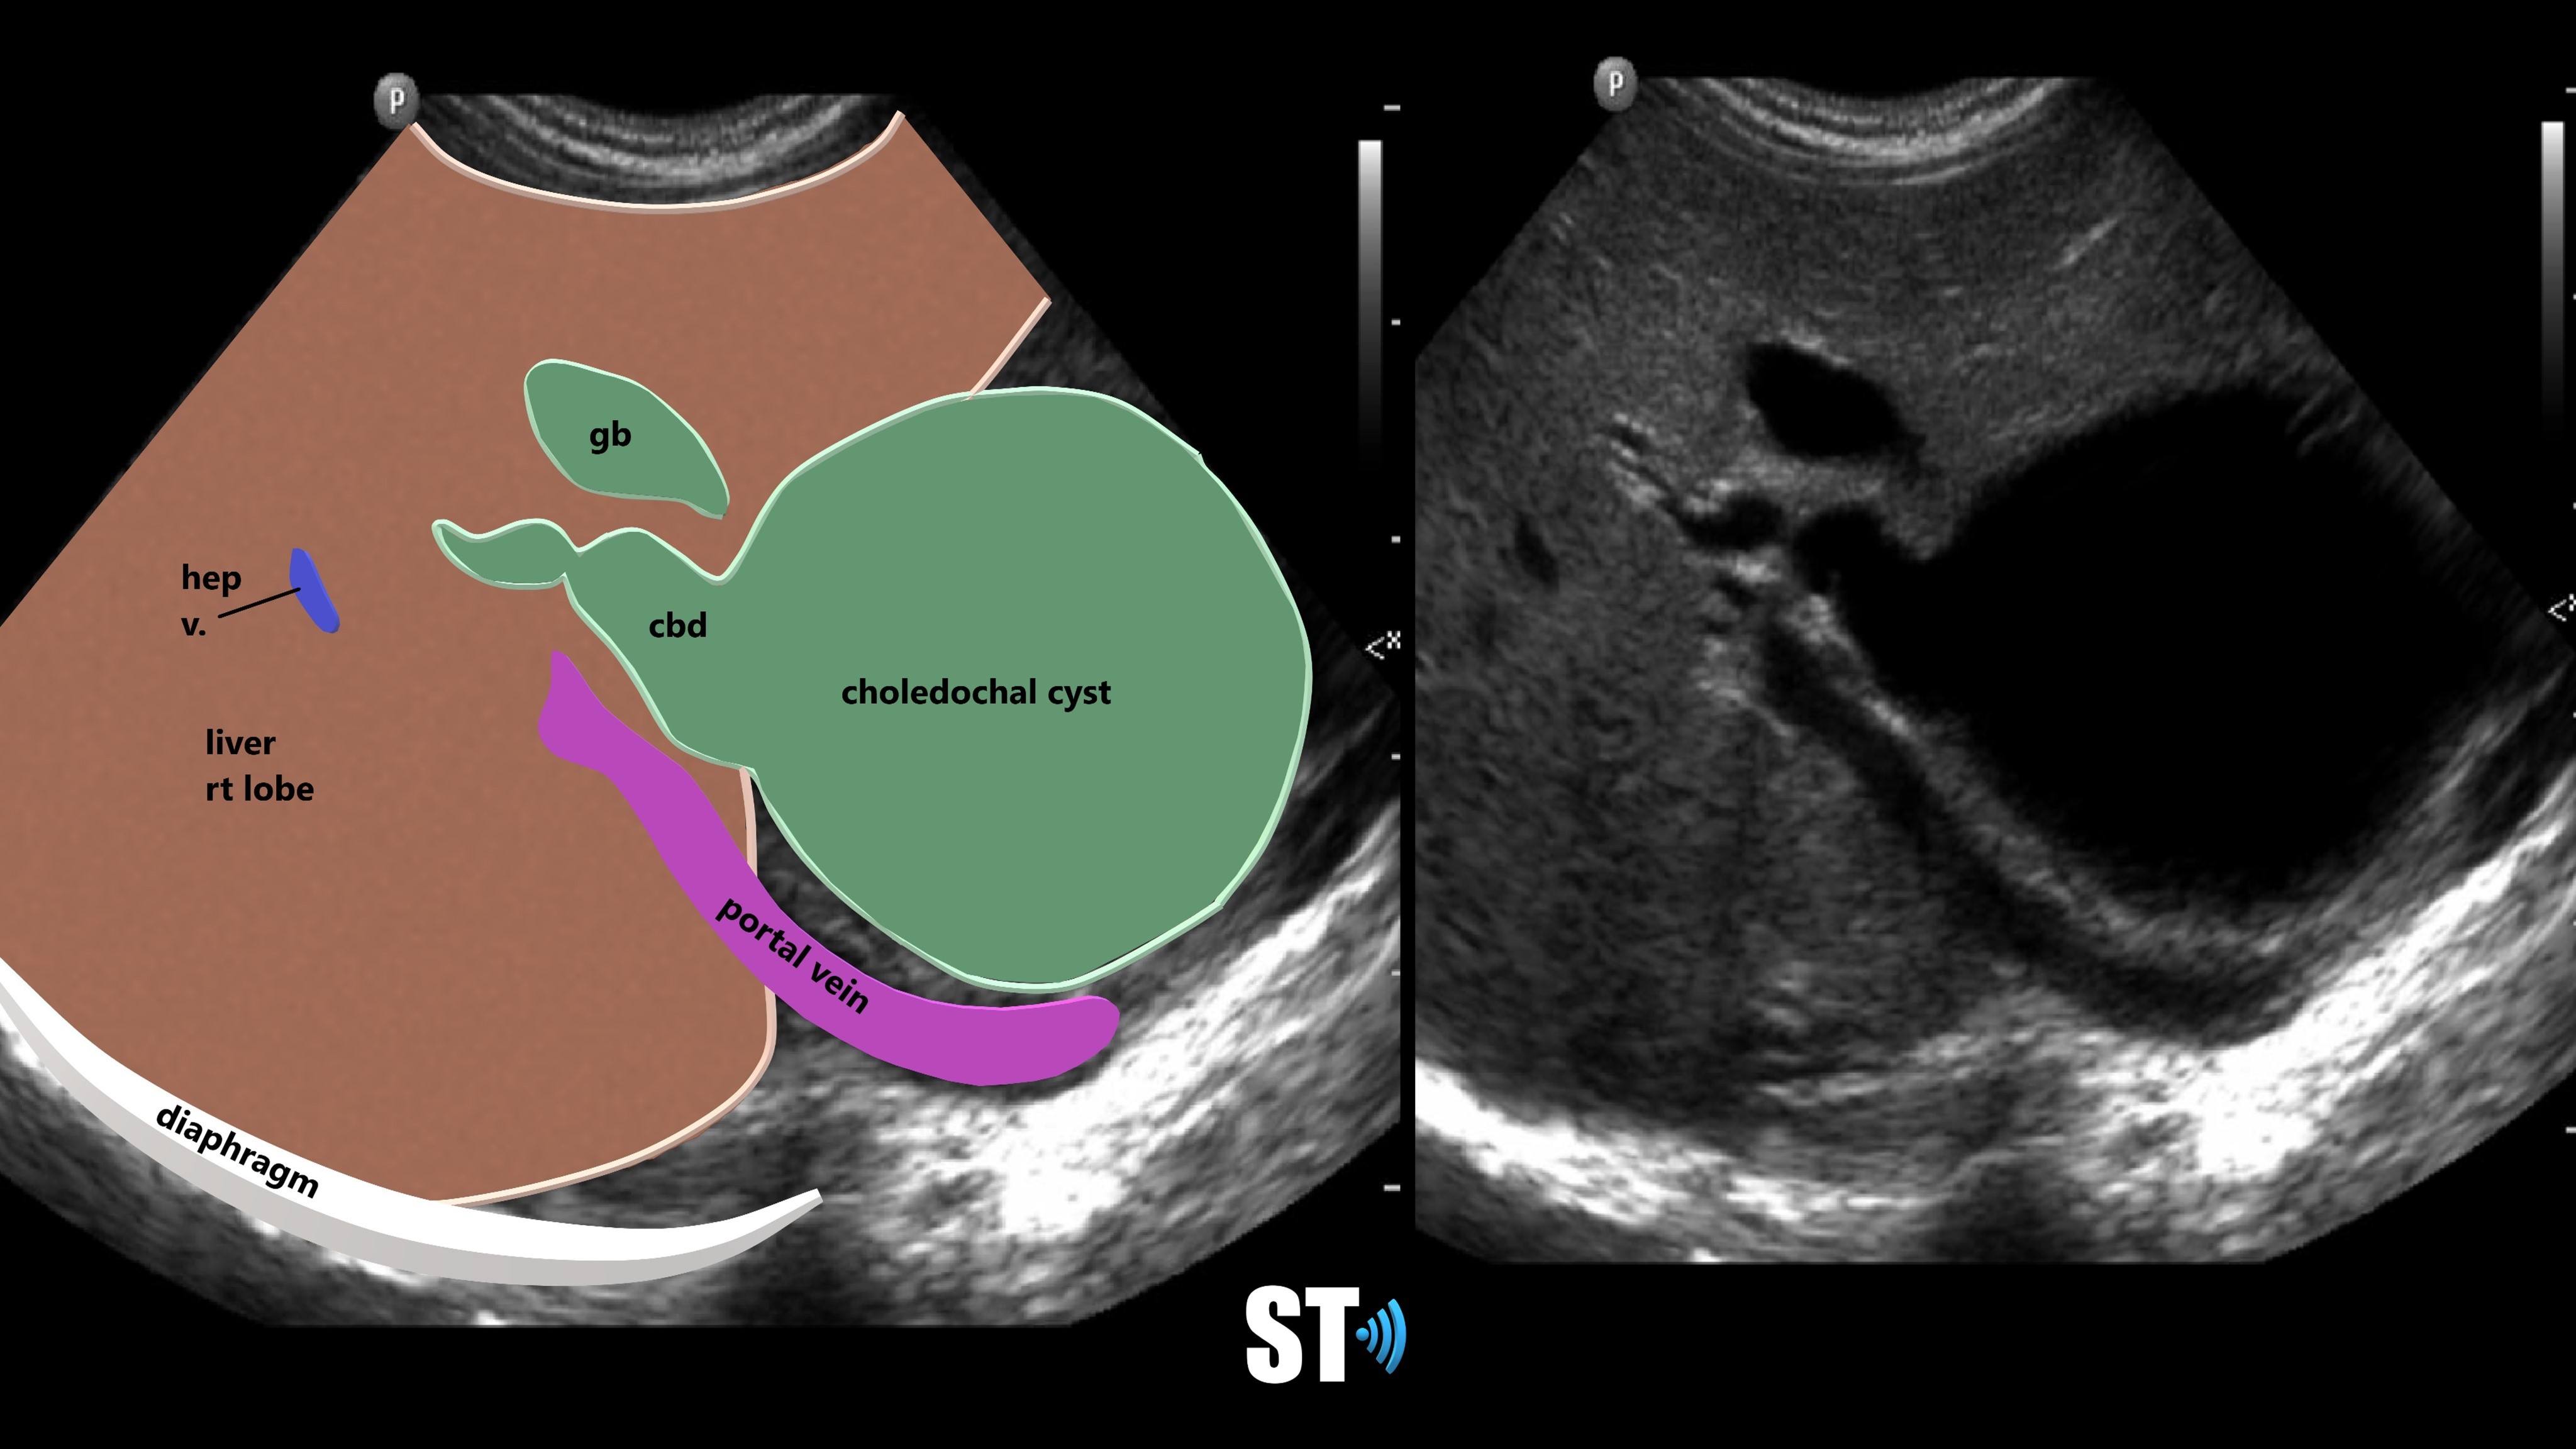

From www.fetalultrasound.com

Ultrasound / Classification of Choledochal Cyst Type Ic Choledochal Cyst Choledochal cyst is a congenital cystic dilation of a part of bile duct that occurs most commonly in the main part of common. Biliary cysts, also termed choledochal malformations, are cystic dilations that may occur singly or in multiples throughout. Type i cysts are a dilatation of the extrahepatic bile duct. A choledochal cyst (cc) or biliary cyst is a. Type Ic Choledochal Cyst.

Ultrasound / Classification of Choledochal Cyst Type Ic Choledochal Cyst A choledochal cyst (cc) or biliary cyst is a congenital or acquired anomaly affecting the biliary tree. Choledochal cyst is a congenital cystic dilation of a part of bile duct that occurs most commonly in the main part of common. Type i cysts are a dilatation of the extrahepatic bile duct. Characterized by fusiform dilation of the extrahepatic bile duct.. Type Ic Choledochal Cyst.

Ultrasound / Classification of Choledochal Cyst Type Ic Choledochal Cyst Characterized by fusiform dilation of the extrahepatic bile duct. Type i cysts are a dilatation of the extrahepatic bile duct. Choledochal cyst is a congenital cystic dilation of a part of bile duct that occurs most commonly in the main part of common. Biliary cysts, also termed choledochal malformations, are cystic dilations that may occur singly or in multiples throughout.. Type Ic Choledochal Cyst.